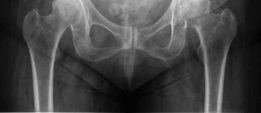

Standard antero-posterior and cross-table lateral radiographs of the pelvis and left hip were obtained immediately following the primary clinical assessment.

The initial AP pelvis radiograph clearly demonstrated a displaced left femoral neck fracture. The fracture line was entirely intracapsular. The femoral head was superiorly and posteriorly displaced relative to the femoral neck, with evidence of approximately 1.5 cm of shortening. The bone quality appeared reasonable for the patient's age, with a preserved Singh index and cortical thickness in the diaphyseal region, though some osteopenia was evident in the proximal trabecular patterns. No signs of pre-existing significant hip osteoarthritis (such as joint space narrowing, subchondral sclerosis, or osteophytosis) in the ipsilateral joint were noted. The contralateral hip appeared unremarkable.

Further radiographic views confirmed the complete displacement and the lack of cortical contact between the proximal and distal fragments. The fracture was classified as a Garden Type IV, indicating complete displacement with a loss of trabecular alignment between the femoral head and the acetabulum, where the head has rotated independently of the neck. Furthermore, it was classified as a Pauwels Type III, meaning the fracture line angle was greater than 70 degrees from the horizontal. This vertical fracture orientation indicates extremely high shear forces across the fracture site, portending a very poor prognosis for osteosynthesis and a high risk of nonunion or fixation failure if internal fixation were to be attempted.